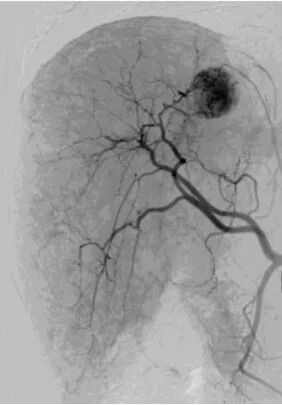

肝脏肿瘤染色